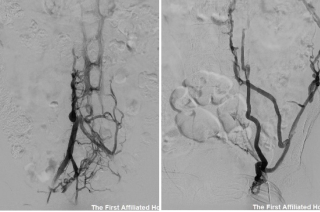

两周前,来自宁夏回族自治区固原市的患者杨先生突发心前区疼痛,于当地医院诊断为“急性ST段抬高性心肌梗死(广泛前壁)”,急诊行冠脉造影见:左前降支近段完闭塞,立即给予球囊扩张、冠脉内溶栓及血栓抽吸等治疗后,管腔仍存有附壁血栓,但血流恢复,症状缓解。因患者既往合并“布加综合征、下腔静脉血栓、左髂静脉血栓、肺栓塞”病史,病情复杂且危重,当地建议转上级医院进一步诊治。患者与家属慕名来到西安交大一附院结构性心脏病科就诊。接诊的魏峰副主任医师详细询问患者病情后,考虑患者并非单纯的传统意义上的心肌梗死,由静脉血栓反常栓塞至冠脉导致急性心肌梗死可能性大。遂即完善了冠脉造影、心动超声、右心声学造影检查。冠脉造影显示左右冠脉完全正常,左前降支管壁光滑,无狭窄、夹层及血栓影;心动超声示:前间隔、左室前壁搏幅减低,卵圆孔未闭;右心声学造影示:Valsalva动作后即刻左心可探及大量微气泡;动态心电图未监测到房颤等心律失常。反常栓塞RoPE(Riskof Paradoxical Embolism)评分7分,以上高度提示反常栓塞。胡志副教授看过病人后考虑此病例罕见,静脉血栓经开放的卵圆孔栓塞于冠状动脉引起心肌梗死的可能性大,封堵卵圆孔可预防再次出现心、脑等重要脏器致命性栓塞,但患者既往存在下腔静脉狭窄伴血栓形成,需评估下腔静脉手术入路;同步下腔静脉造影显示左髂静脉及下腔静脉肝下段血栓形成,管腔狭窄、闭塞,奇静脉开放伴大量侧枝静脉回流建立(图1)。

图1下腔静脉阻塞